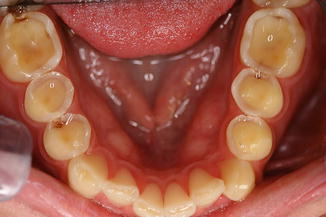

4. 탄산수 섭취 후 치아 표면의 변화

여러 음료에 치아를 4시간, 12시간 노출시켰을 때 치아표면의 변화를 살펴 보겠습니다.

증류수(Distilled water)와 비교하였을 때 대부분의 음료들이 치아 표면을 침식 시킨 것이 관찰됩니다.

탄산수에 의해서 법랑질 표면이 손상된 사진을 보셨습니다.